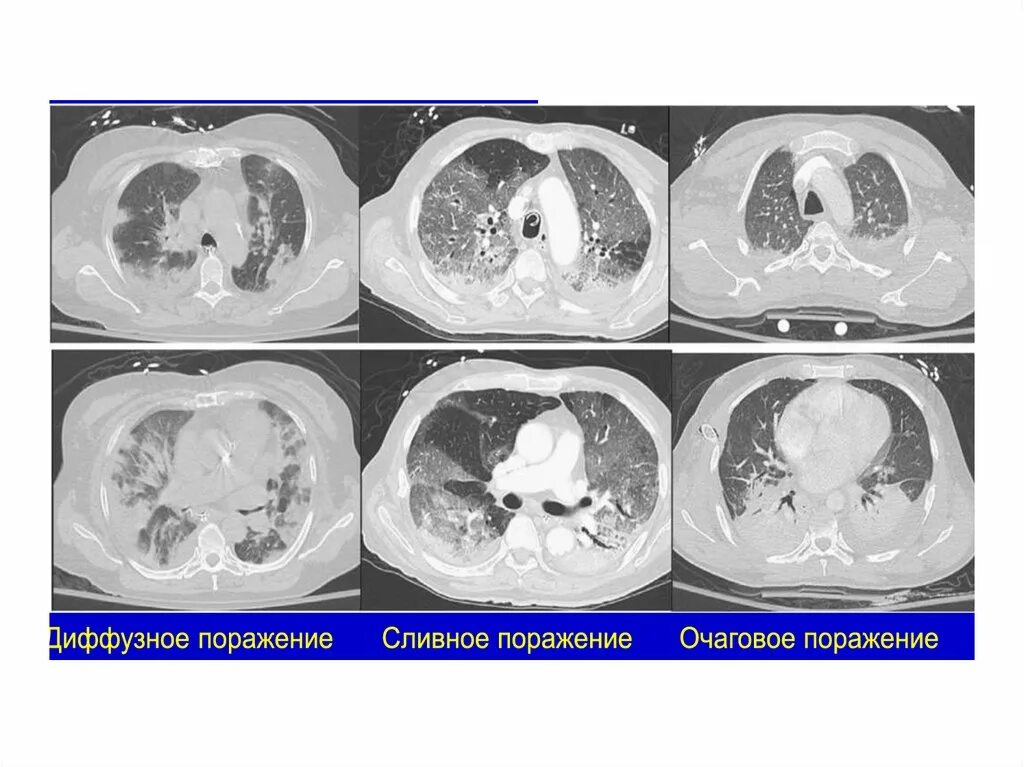

Ордс крипта